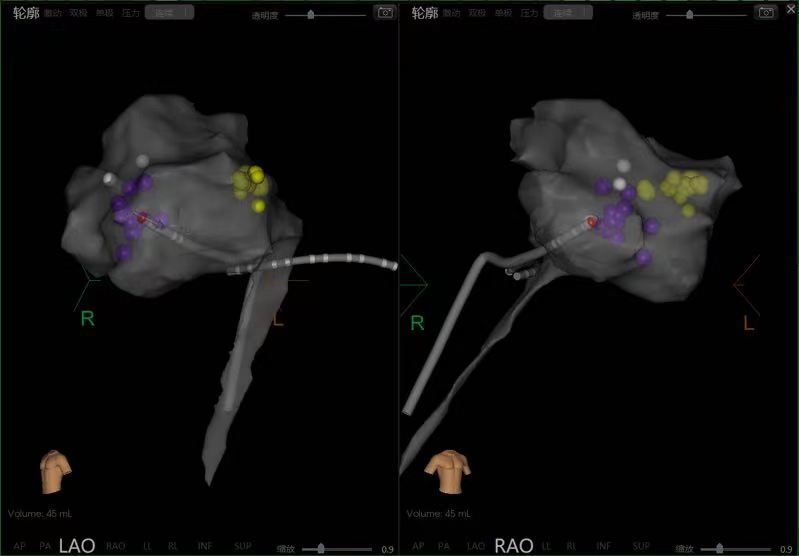

三维模型图

消融后反复验证,患者无室上速发作,无“跳跃现象”,术中患者无明显不适,手术成功。